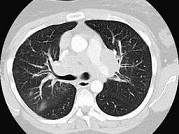

单项选择题女,33岁, 咳嗽,无发热, 结合图像,最可能的诊断是 ( )

A、肺结节病

B、淋巴瘤

C、中央型肺癌

D、胸腺瘤

E、支气管囊肿